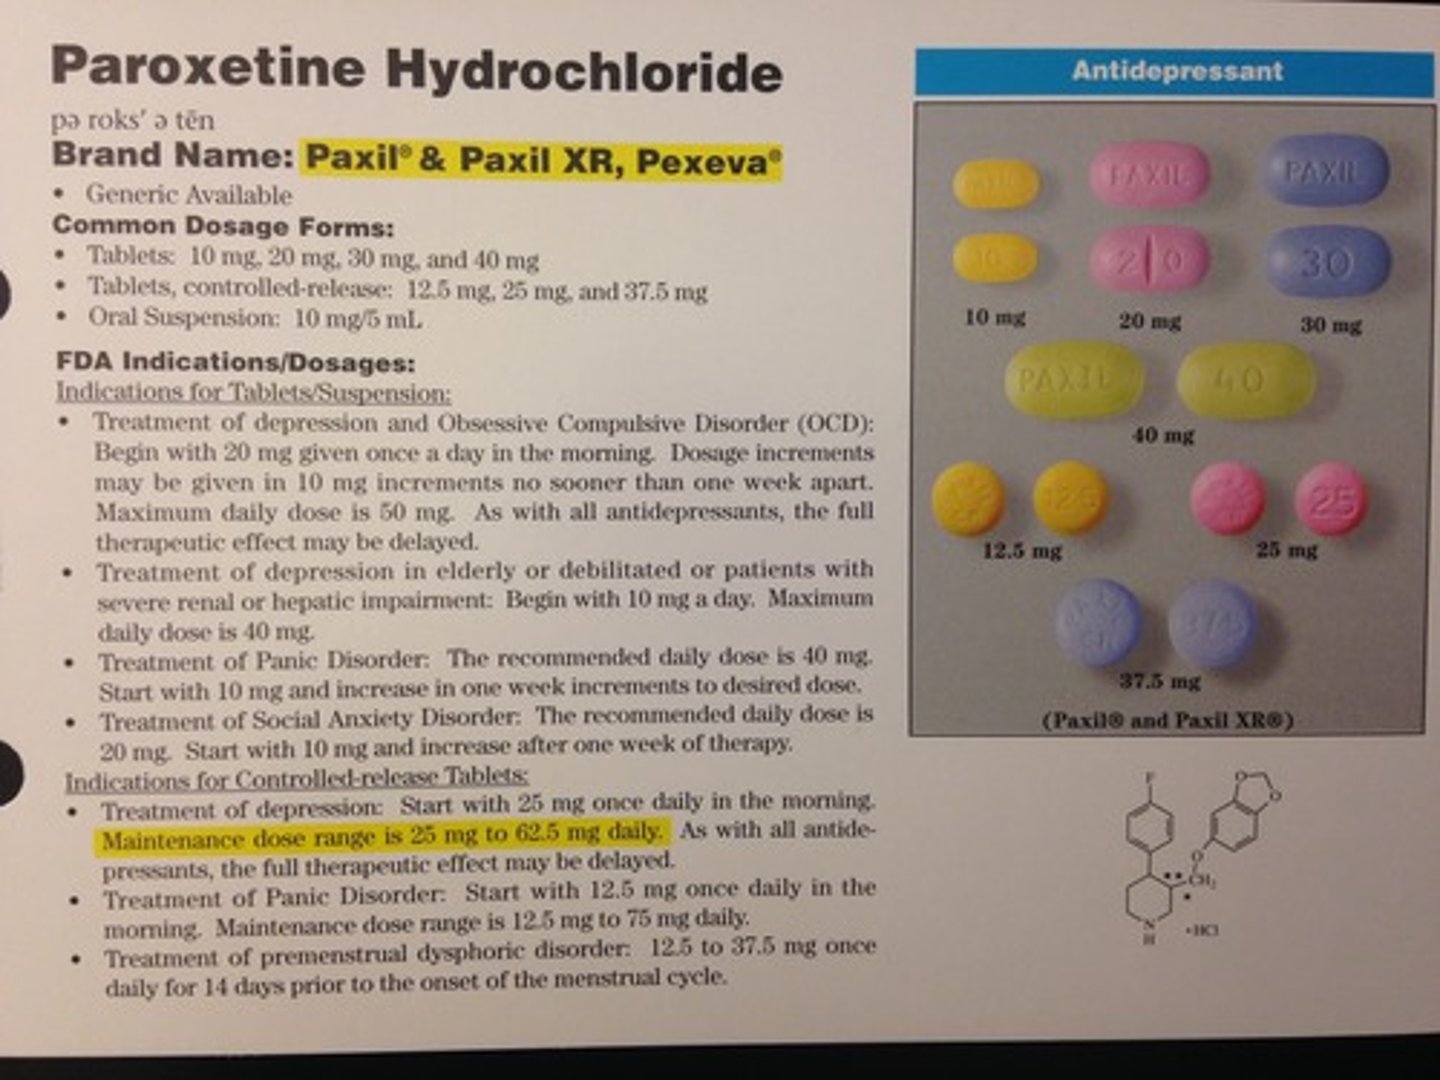

Paroxetine

Brand: Paxil

Class: SSRI

Interaction: Serotonin Syndrome with MAOIs

Indication: Antidepressant

Schedule: NCLM